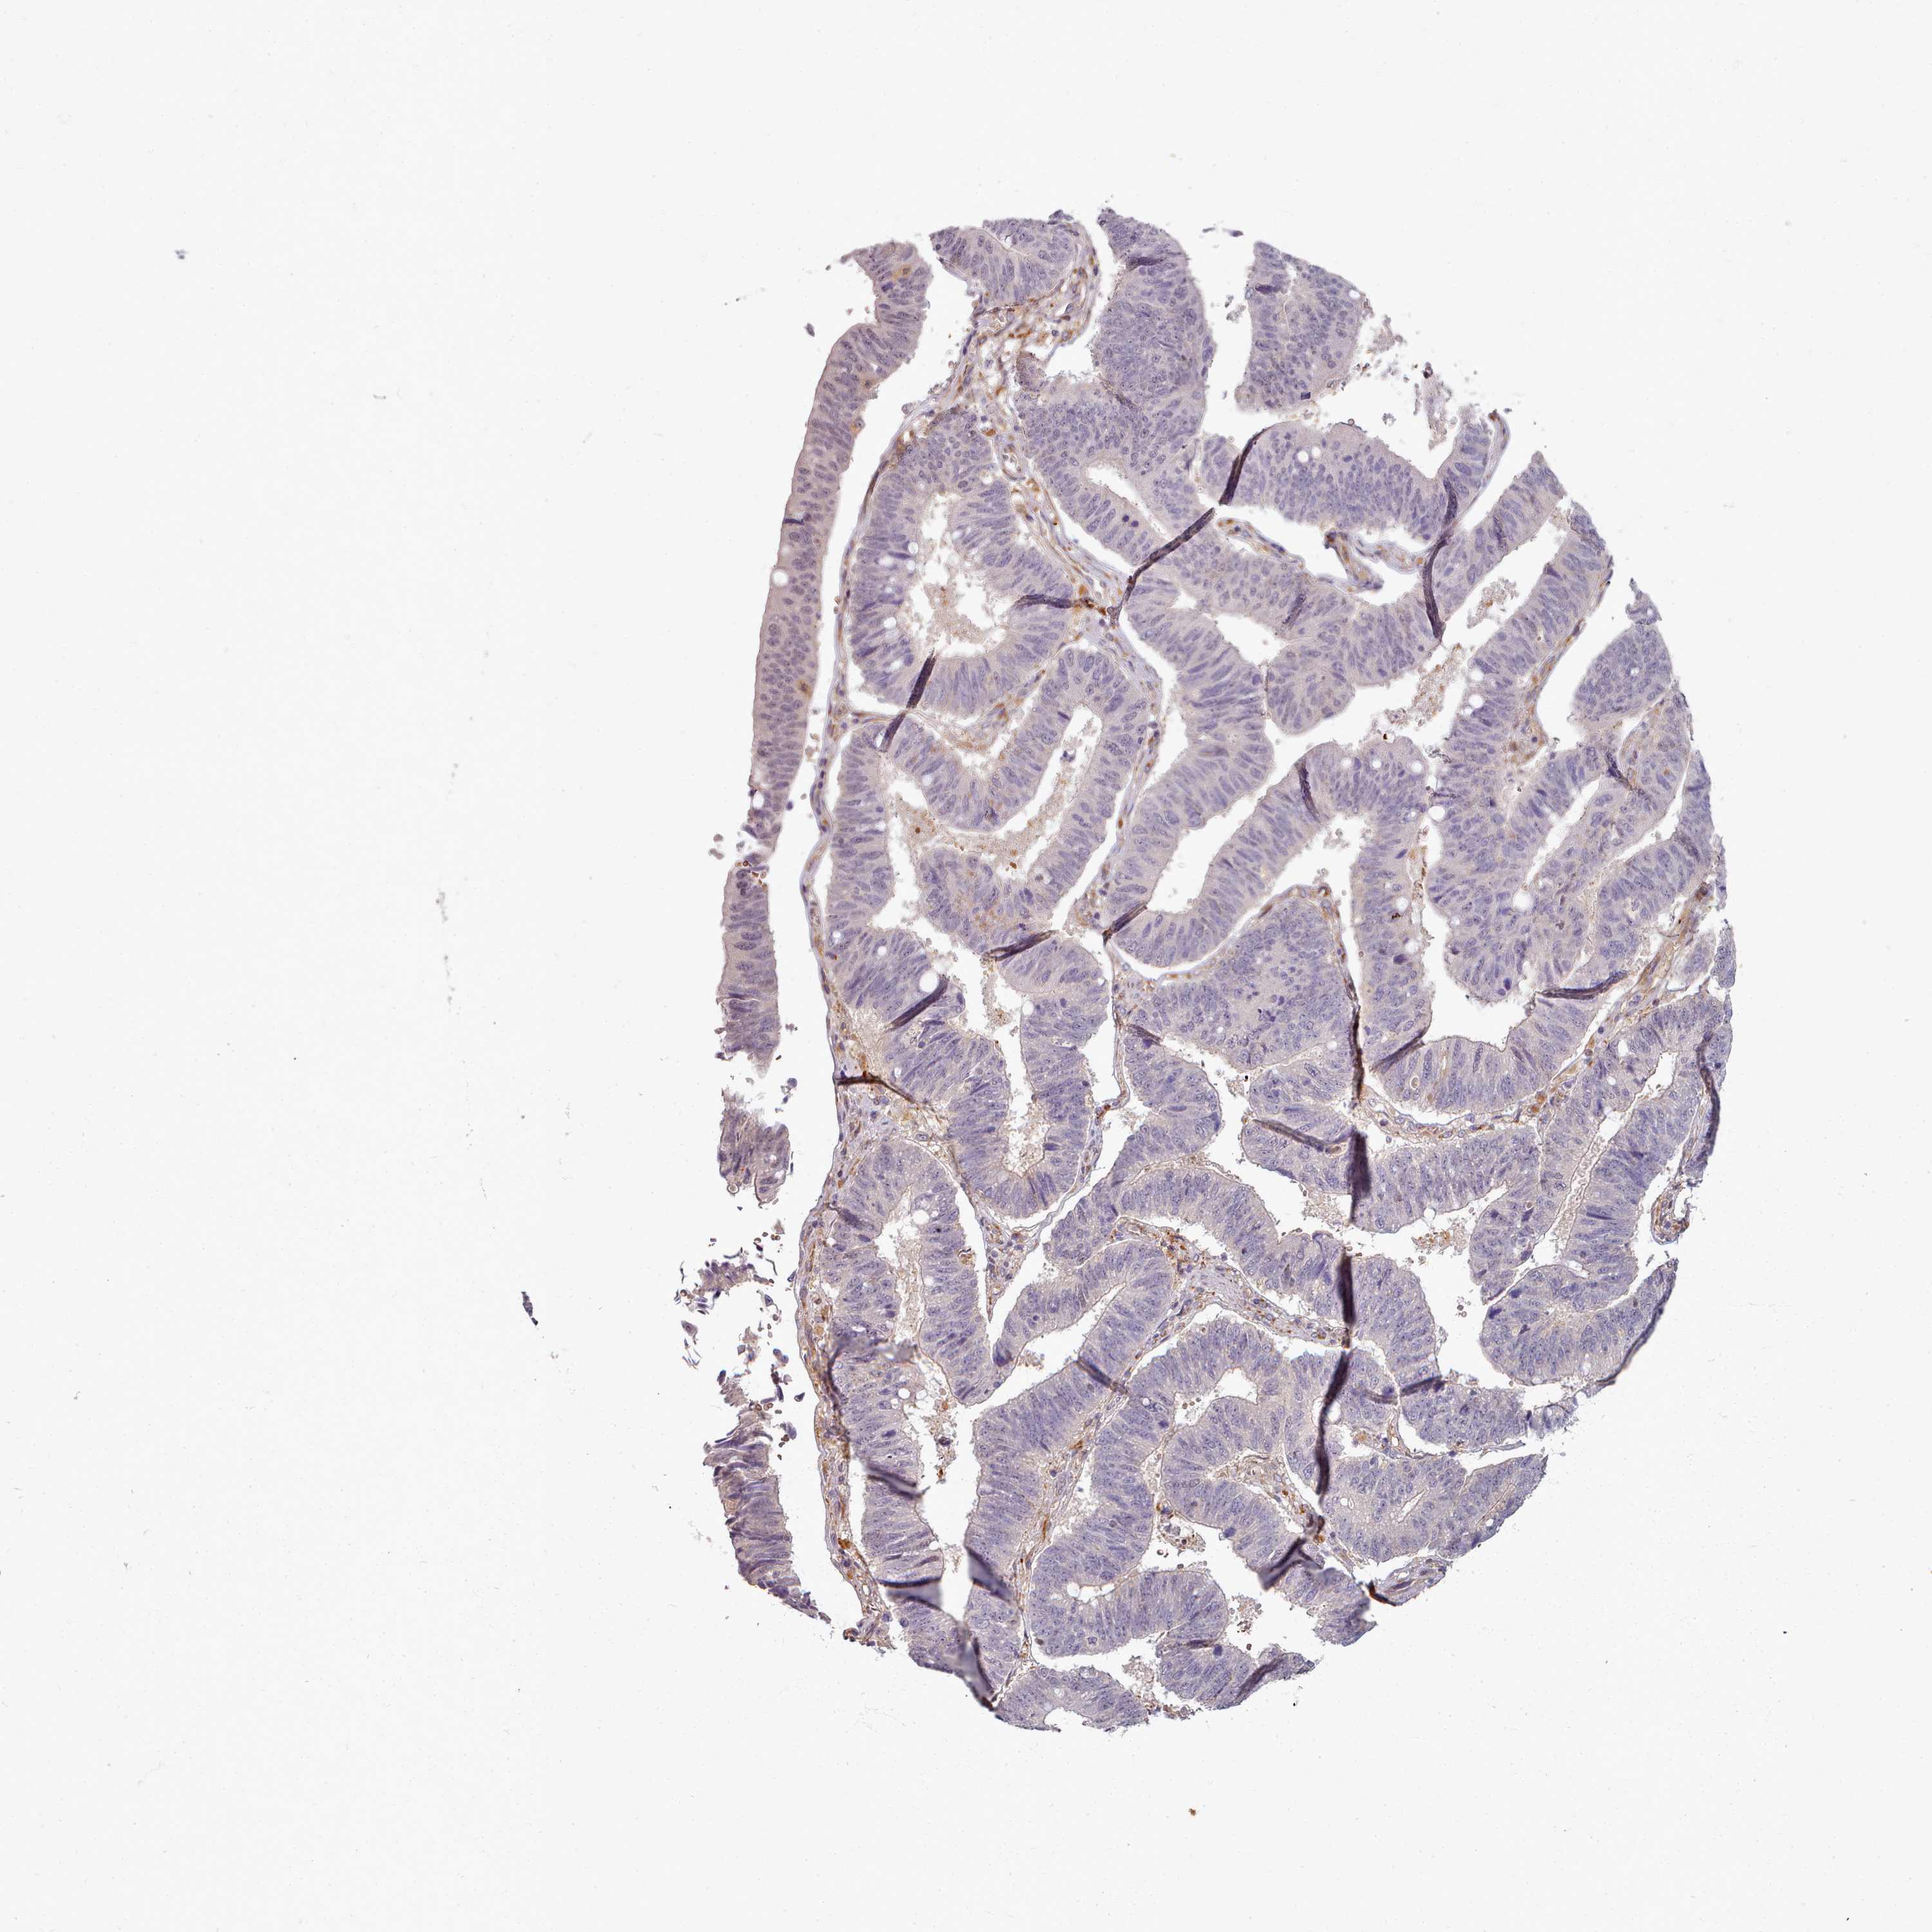

STOMACH CANCER - Protein expressioni

A mouse-over function shows sample information and annotation data. Click on an image to view it in a full screen mode. Samples can be filtered based on level of antibody staining by selecting one or several of the following categories: high, medium, low and not detected. The assay and annotation is described here.

Note that samples used for immunohistochemistry by the Human Protein Atlas do not correspond to samples in the TCGA dataset.

Antibody stainingi

Antibody staining in the annotated cell types in the current human tissue is reported as not detected, low, medium, or high, based on conventional immunohistochemistry profiling in selected tissues. This score is based on the combination of the staining intensity and fraction of stained cells.

Each image is clickable and will lead to virtual microscopy that enables deeper exploration of all samples and also displays staining intensity scores, fraction scores and subcellular localization as well as patient and tissue information for each sample.

Antibody HPA038604

Antibody CAB025607

Staining

High

Medium

Low

Not detected

Intensity

Strong

Moderate

Weak

Negative

Quantity

>75%

75%-25%

<25%

None

Location

Nuclear

Cytoplasmic/membranous

Cytoplasmic/membranous,nuclear

Adenocarcinoma, NOS